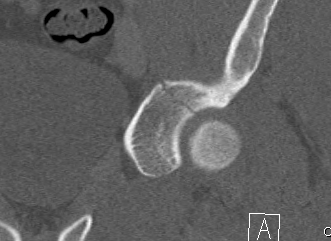

CT

Configuration

1-2 mm sections

CT reconstruction

- remove head to view acetabulum

- beware volume averaging

- used to guide surgery

Diagnose

Loose bodies

Femoral head fractures

Subtle subluxation

Articular steps

Roof arc measurement

3. Stability / Concentric reduction

Subluxation

- incongruency between the head and the roof

- poor clinical results are obtained in more than 50% of fractures in which the head is subluxed

- may also have an element of dynamic instability, with certain posterior wall fractures

Any subluxation on CT demonstrates clinical instability

- fractures affecting 40% or more of the posterior wall are usually associated with instability

- fractures less than 40% should be screened for stability under II